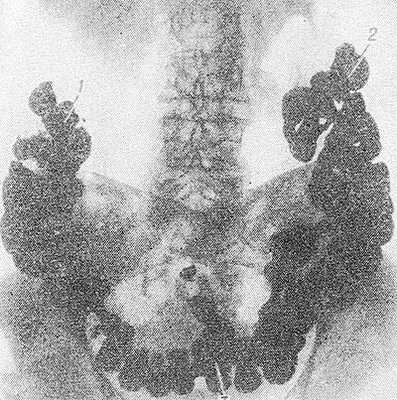

Рис. 3. Рентгенограмма брюшной полости больного с колоптозом (прямая проекция) после перорального контрастирования толстой кишки: печеночный (1) и селезеночный (2) изгибы ободочной кишки расположены низко, поперечная ободочная кишка (3) провисает в малый таз.

При опущении толстой кишки определяется низкое положение печеночного и селезеночного ее изгибов, а также слепой и поперечной ободочной кишок. При этом чрезмерно подвижная слепая кишка может находиться в малом тазу, куда нередко провисает и имеющая вид гирлянды поперечная ободочная кишка (рис. 3). Рельеф слизистой оболочки остается нормальным. Смещаемость кишки при отсутствии спаек не нарушена. В опущенной и удлиненной кишке могут наблюдаться дополнительные петли, перегибы, повышение или понижение тонуса, замедление пассажа содержимого. Задержка контрастного содержимого может достигать 96 час. и более. Опущение отделов кишечника необходимо дифференцировать с их вторичным смещением, обусловленным объемным или рубцово-спаечным процессом в брюшной полости или забрюшинном пространстве.